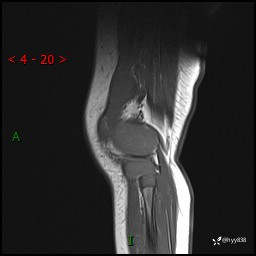

现病史:患儿1月前无明显诱因出现左下肢跛行,伴左膝关节红肿,无发热、咳嗽、恶心、呕吐等症,于当地医院就诊行X线片未提示异常,今至我院门诊就诊,门诊医师拟“跛行待查”收入院。 病后,患儿精神、食欲可,睡眠欠安,大小便通畅,体力体重无明显下降。

左膝MRI平扫